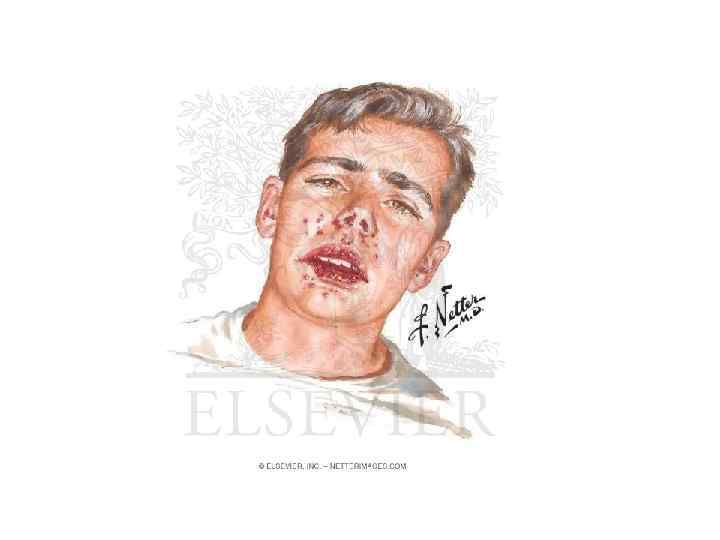

Долевая пневмония (плевропневмония). Начальная стадия Внезапное начало заболевания: • • • повышение температура до 39 – 40 градусов с ознобом, головной болью, резкой слабостью боль в грудной клетке при дыхании на стороне поражения, усиливающейся при вдохе и кашле, кашель, вначале непродуктивный, а через 1 - 2 дня с вязкой мокротой, может быть «ржавой» или слизисто-гнойной. одышка разной степени выраженности Объективные данные: При осмотре отмечается гиперемия щек, цианоз губ, со 2 – 3 дня нередко появляются герпетические высыпания на крыльях носа, губах, вынужденное положение на больном боку. отставание грудной клетки на стороне поражения при дыхании, голосовое дрожание ослаблено. при перкуссии укорочение перкуторного звука над областью поражения (в первые часы может быть тимпанит), переходящее в тупой звук. при аускультации ослабленное везикулярное дыхание, крепитация, при плевральной реакции – шум трения плевры.